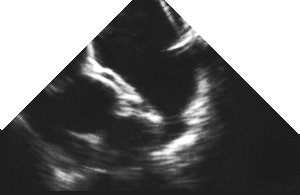

1. Four chamber view (ME 4 Chamber)

2. UP Mid-oesophageal four chamber view CLICK FOR VIDEO: four chamber view (mid-oesophageal)

In the picture from the visible human slice server on the left, note how dilated the right side of the heart is, with the left side extremely poorly filled (This isn't normal). You can still however still see all four chambers clearly, with the interatrial septum bulging into the left atrium! Three of the chambers are labelled (RA, LA, RV) - but the left ventricle is also clearly identifiable. You can also clearly delineate the mitral valve (mv), tricuspid (tv) and lateral wall of the left ventricle (lw). In the echo image, you can actually also see the start of the LV outflow tract, so technically this is a 'five-chamber' view (see below).

Obtaining the view

This view is usually obtained with the probe 35-37 cm from the incisor teeth. Note that good views of the mitral valve are obtained, and the interatrial septum is also well seen, but the apex of the left ventricle is usually not well seen, precluding assessment of ventricular function.